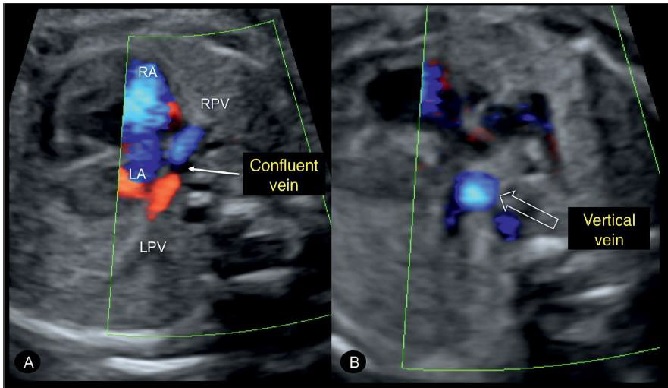

Hình 8: (A) Hình ảnh Doppler màu mặt cắt ngang ngực thai thi có bất thường hồi lưu tĩnh mạch phổi toàn phần (TAPVR). Chú ý tĩnh mạch phổi phải (RPV) và tĩnh mạch phổi trái (LPV) không đổ vào nhĩ trái mà đổ vào tĩnh mạch thu thập (confluent vein), ngăn cách với nhĩ trái bởi một dải mỏng. (B) Tịnh tiến đầu dò về phía đầu thai nhi thấy hình ảnh mặt cắt ngang tĩnh mạnh đứng dọc (vertical vein) ở trong lồng ngực (mũi tên rỗng).

Một trong những hình ảnh chính trong chẩn đoán là khảo sát kỹ mặt cắt 4 buồng tim. Trong nhiều trường hợp thấy hình ảnh một cấu trúc ống phía sau tâm nhĩ trái, được gọi là tĩnh mạch hợp lưu (confluent vein). Trong TAPVR không có tĩnh mạch phổi nào đổ vào nhĩ trái, mà chúng đổ vào tĩnh mạch hợp lưu (confluent vein).

2.2 Siêu âm Doppler màu chẩn đoán TAPVR trước sinh:Siêu âm Doppler màu và Doppler xung rất có ý nghĩa trong TAPVR. Khi nghi ngờ có tĩnh mạch hợp lưu phía sau nhĩ trái ở mặt cắt 4 buồng nên sử dụng Doppler màu với thang vận tốc màu thích hợp (Ghi chú của người hiệu đính: theo guidelines 2013 của ISUOG, với dòng chảy tĩnh mạch phổi, thang vận tốc màu nên để ở mức 30 cm/s). Điều chỉnh thang tốc độ màu là rất cần thiết để tránh chẩn đoán sai và dương tính giả. Kiểm tra hỉnh ảnh phổ Doppler xung của tĩnh mạch phổi bất thường so sánh với tĩnh mạch phổi bình thường có vận tốc khác nhau không cũng là một gợi ý. Các kết nối bất thường của tĩnh mạch phổi cũng có thể phát hiện ở Doppler màu mặt cắt theo trục dọc cơ thể.

Tình trạng này có thể quan sát thấy bằng cách phát hiện thấy tĩnh mạch hợp lưu phía sau nhĩ trái (Hình 1B). Tại mặt cắt 3 mạch máu - khí quản, ta có thể thấy một mạch máu thứ tư đó là tĩnh mạch dọc, nó được nhìn thấy ở vị trí giải phẫu giống như một tĩnh mạch chủ trên bên trái (LSVC) (Hình 1B). Nhưng trong tồn tại tĩnh mạch chủ trên trái (PLSVC), máu từ tĩnh mạch cổ trong trái (left internal jugular vein) chảy theo chiều từ trên xuống thông qua LSVC về tim, còn dòng máu trong tĩnh mạch dọc trên trong thể trên tim của TAPVR lại chảy theo chiều ngược lại từ tim lên phía đầu. Doppler màu trên mặt cắt 3 mạch máu khí quản cho phép ta đánh giá chiều dòng chảy của các cấu trúc giải phẫu này.